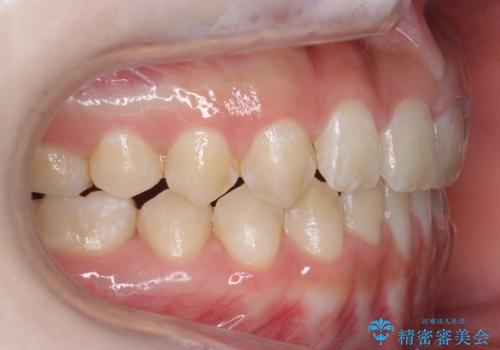

隙間を閉じる際、奥歯が倒れたため、途中ワイヤー矯正を併用しています。

上の前歯の隙間を閉じながら前歯を後方に下げているため、口元もひっこみ、口が閉じやすくなりました。